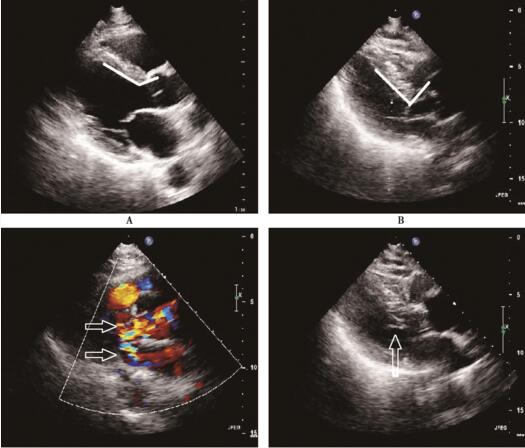

复查超声心动图:各房室大小正常;基底段室间隔凸向左心室流出道,主动脉与室间隔夹角变小,导致左室流出道狭窄,收缩期二尖瓣前叶及腱索前向运动 (SAM征);多普勒血流频谱示左心室流出道快速血流和二尖瓣反流形成双束分叉血流。诊断为S型室间隔并左心室流出道狭窄、左心室舒张功能下降、左心室收缩功能正常(图95-2、95-3)。口服β受体阻滞剂、抗血小板药物治疗后,患者好转出院。

图95-2 超声心动图胸骨旁在心室长轴切面图像 A:正常人左心室流出道室间隔与主动脉夹角呈钝角;B:本例该患者左心室流出道室间隔与主动脉夹角变小呈近似直角;C:本例患者左心室流出道收缩期快速血流与二尖瓣前叶收缩期前向运动,引起二尖瓣反流共同构成特征性分叉血流;D:二尖瓣前叶腱索收缩期前向运动

S形室间隔导致左心室流出道梗阻的机制迄今尚未明确,可能与长期高血压或主动脉粥样硬化有关。有学者认为,S形室间隔为肥厚型心肌病亚型。但随后研究发现S形室间隔与肥厚型心肌病有所不同,前者病理改变为心内膜纤维组织增厚、轻度心肌间质纤维化而无心肌细胞排列紊乱。S形室间隔患者超声心动图可特征性表现为室间隔基底部增厚并突入左心室流出道,同时增厚的室间隔使室间隔与主动脉间夹角变小。正常人此角度>120°(图95-1A),S形室间隔患者角度明显减小,与增厚的室间隔基底部共同引起左心室流出道梗阻(图95-1B)。

左心室流出道梗阻患者存在SAM现象的可能机制:①左心室流出道狭窄致血流速度加快,流出道为相对负压,吸引二尖瓣前叶、腱索前向运动,即Venturi效应;②由于肥厚的室间隔收缩运动减弱,左心室后壁代偿性运动增强,后基部的有力收缩迫使二尖瓣前叶进入血液几乎排空的左心室流出道;③由于乳头肌排列紊乱,心脏收缩时肥厚的室间隔挤压绷紧的腱索致腱索后移,而二尖瓣前叶上翘前移。由于左心室流出道狭窄和二尖瓣前叶收缩期前向运动,造成多普勒血流频谱呈现特征性左心室流出道快速血流和二尖瓣反流形成的双束分叉血流(图95-1C)。

本例患者由于患急性冠状动脉综合征,应用硝酸酯类药物后杂音变响;并发心力衰竭后由于心肌收缩力减低,左心室流出道压差减小致杂音减弱,而在心力衰竭控制后杂音增强;患者坐位时因回心血量减少使杂音增强,平卧位时回心血量增加而杂音减弱,故杂音不断变化致临床表现不同寻常。超声心动图表现为室间隔基底部增厚,增厚的室间隔与主动脉间角度变小导致左心室流出道梗阻、SAM征,以及左心室流出道快速血流和二尖瓣反流形成双束分叉血流。